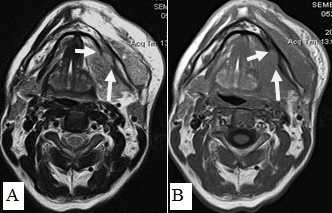

Сложно было с помощью МРТ визуализировать опухоли любых размеров с поверхностным распространением, не выходящие за пределы слизистой оболочки. Опухоли малых размеров (Т1 стадия) в 2 наблюдениях были однородны, не имели центральной зоны некроза и сливались с мышцами. С увеличением размера опухолевого узла отмечалась неоднородность структуры. В наших исследованиях удалось выявить небольшие опухоли Т1 и Т2 стадий, локализованные в области языка и дна полости рта. В 9 наблюдениях опухоли Т2 стадии, не накапливающие контраст при МСКТ исследовании, хорошо визуализировались при МРТ в режимах Т2-ВИ, STIR, проявляясь сигналом высокой интенсивности. Можно было четко видеть границы опухоли и оценить ее размеры (рис. 9,10).

Рис. 10. А. Пациент Е., 52 года. МРТ полости рта, ротоглотки в аксиальной проекции, Т1-ВИ. Опухоль языка небольших размеров, границы визуализируются с трудом за счет перифокального отека (стрелки); В. Тот же пациент. МРТ в аксиальной проекции, Т2 с подавлением сигнала от жировой ткани. Визуализируются границы опухолевого узла, размеры опухоли языка четко определяются (стрелки)